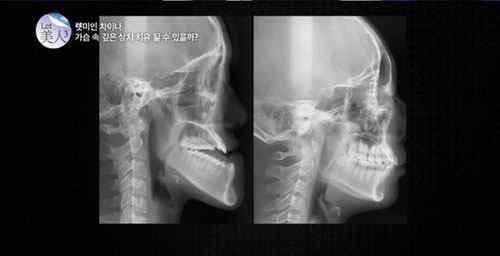

在日前播出的《让美》节目上的故事里,播出了节目最早制作的《让美中国》。在这个项目中,“有牙齿的女孩”郭方圆被许多申请者选中——她从小就被昵称为“外星人”,因为她的下巴出奇的长。虽然她才18岁,从3岁从椅子上摔下来,上颚几乎停止生长,但是下颚却越长越长,变成了现在的样子。除了外表,她还因为牙齿而难以咀嚼食物。

手术60天后,郭方圆的外貌完全变了样,被称为“拥有一张既令人羡慕又让人惊喜的芭比娃娃般的脸”。郭方圆的父母告诉参与节目的人:“我们不认女儿。她的下巴好多了。现在想来,送女儿去韩国是个明智的决定。